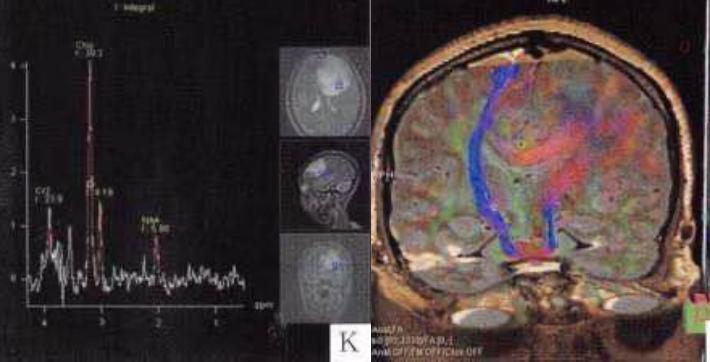

男性,出生2月余,喂食差,癫痫,呕吐,低血糖。

答案:枫糖尿病。枫糖尿病是由α-酮酸脱氢酶多酶复合体功能缺陷引起的常染色体隐性遗传病。婴儿起病的白质脑病要想到枫糖尿病。影像上要注意和Leigh综合征鉴别。Leigh综合征多在10岁以前发病,以婴幼儿多见;神经系统的主要表现为抽搐、卒中发作、眼外肌麻痹、痴呆、共济失调、视神经病变等。Leigh多为双侧对称性分布,病变形态不规则,大小不等,呈斑块状;病变主要累及双侧壳核及导水管周围灰质,也可累及丘脑(尤其是背内侧核)、小脑齿状核、脑干、脑白质和皮质均可受累;MRI呈长T1、长T2信号,T2-FLAIR和DWI像病变信号多不均匀。枫糖尿病特点为弥漫性的脑白质水肿,遍及大脑和小脑半球的TW2I上的高信号,尤其在基底节及脑干区。典型表现为侧脑室旁、基底节区、脑干、小脑T2WI及DWI上的高信号影,DWI显示的更加敏感;MRS在0.9ppm处可发现一个相对特异性的宽峰;同时可见NAA峰的下降及Lac峰的升高。